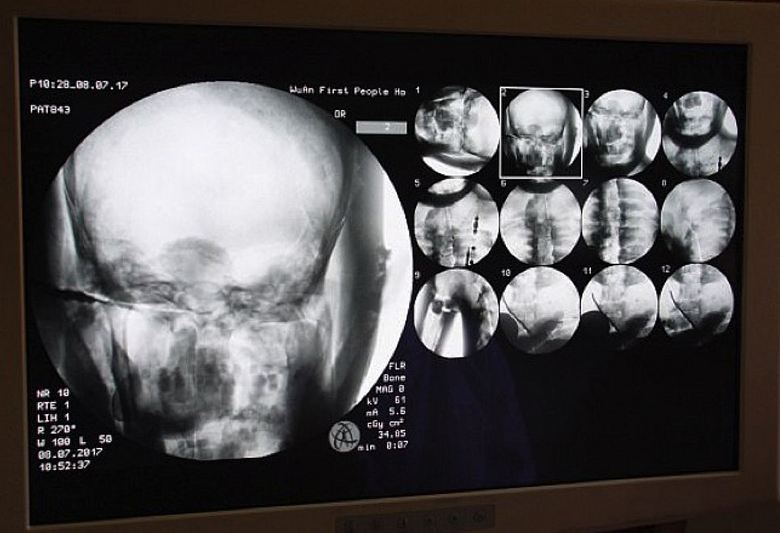

Znanstveniki so se voljno strinjali, saj so se sami zanimali ta zanimiva študija. In 8. julija letos ravno v templju Dinghui je bila narejena tomografija starodavne budistične mumije menih. Tu so zdravniki prinesli potrebno opremo in jo porabili skeniranje notranje vsebine mumije. Bili so šokirani izključno vse, torej ne samo učenjaki, ampak tudi redovniki, romarji, ki so se zbrali na tem neprimerljivem za samostan dogodek, seveda, in medijski delavci. Izkazalo se je, da so sklepi oz. kosti in zob tisoč let starega meniha Tsa Xian so podobni živemu osebo. Še več, njegovi možgani so bili odlično ohranjeni.

Prav neverjetno, je pripomnil doktor Wu. Yongqing (Wu Yongqing), ki je neposredno opravil tomografijo mumije. Sploh ne morem verjeti, kako so glavni deli človeka balzamirano pred več kot tisoč leti, ohranjeno v “zdravo” stanje, celo možgani! Vendar menihi sami niso v tem ne vidijo nič nadnaravnega, prepričani so, da je gospodar Tsy Xian sploh ni umrl, preprosto je stopil v stanje samadhija iz ki se bo nekega dne zagotovo zbudil. Navsezadnje skeniranje mumije pokazal: njegovo telo je pripravljeno na novo življenje …